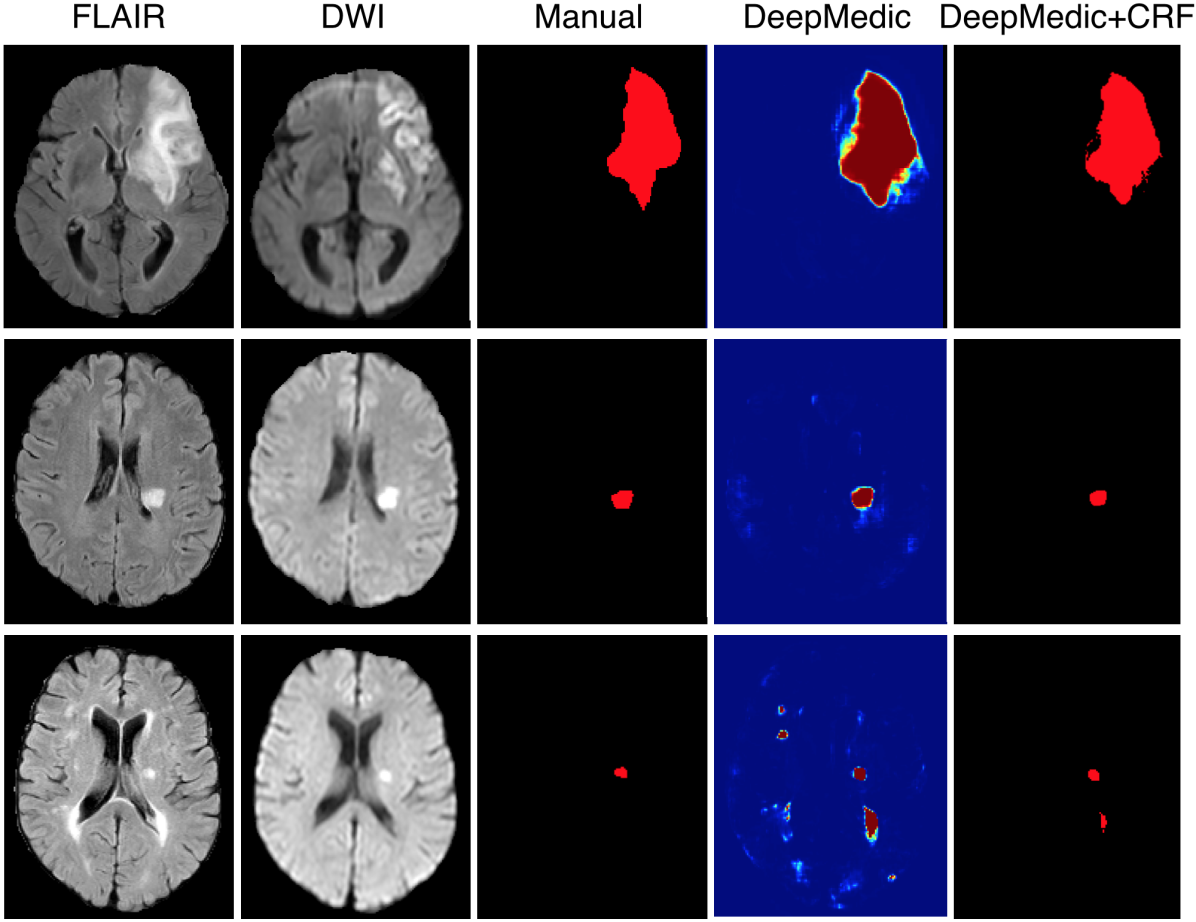

The performance of our system on the training data is shown in Table 4. Significant improvement is achieved by the structural regularisation offered by the CRF, although it could be partially accounted for by overfitting the training data during the CRF’s configuration. Examples for visual inspection are shown in Fig. 13.